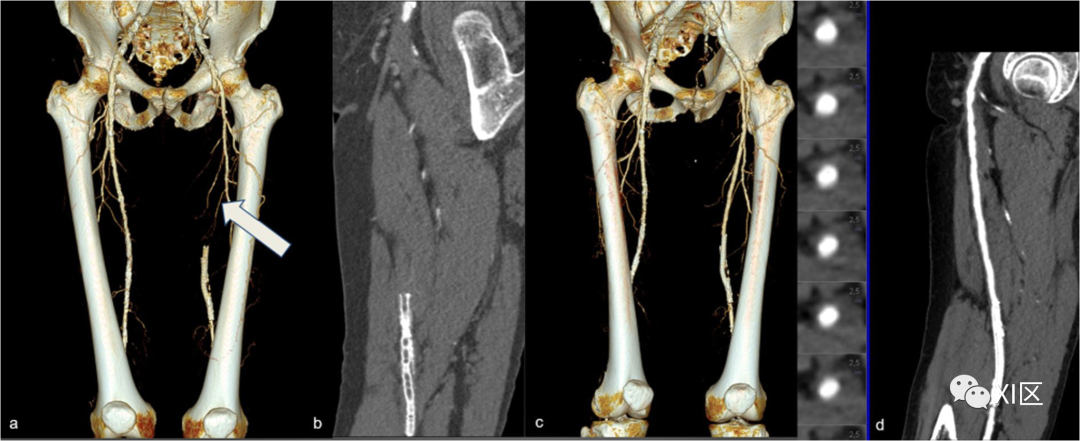

固有动脉的血栓形成通常发生在已有动脉粥样硬化狭窄的部位。CTA表现为一段不存在的腔内强化,伴有或不伴有远端分支的强化(图3和图4)。

图3 天然血管闭塞。显示左股浅动脉起源处闭塞的VR重建(箭头)(a)。CPR(b)显示位于血管下三分之一处的支架没有造影剂充盈。c是血管内治疗8个月后随访检查的VR重建,有证据表明固有血管和支架内管腔(d)显影,在CPR上很明显,管腔内内容物轴位可视化。

图4 腘动脉节段闭塞。73岁男性,突然出现左跛行,下肢CTA。MIP冠状位重建(a)显示左腘动脉的节段性闭塞(箭头),在冠状MIP重建(箭头)(b)中也很明显。在VRT重建中,后视图(c)显示节段性狭窄(箭头);闭塞远端存在血管显影。检查中包括的所有血管段均可见双侧弥漫性动脉粥样硬化改变。